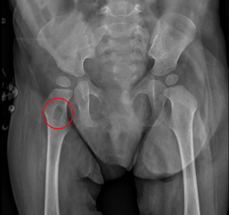

A previously healthy 11-month-old female presented to the clinic with a progressively enlarging retroauricular mass on the left side, noted by her parents for the past two months. There was no associated lymphadenopathy, and the remaining physical examination was unremarkable. Initial laboratory investigations, including complete blood count and inflammatory markers levels, were within normal limits. Given the persistent nature of the mass, biopsy was performed. Histopathological analysis of the biopsy specimen revealed proliferation of atypical cells. Immunohistochemical staining was inconclusive, and further imaging was warranted to characterize the lesion. A metastatic bone series was ordered, revealing two small osteolytic lesions in the neck and right intertrochanteric region of the femur, measuring 1.28 x 0.53 cm and 0.51 x 0.19 cm, respectively (Figure 1). Based on these findings, a preliminary diagnosis of a malignant process, such as a rhabdoid tumor, was considered.

Figure 1 X-ray images of the patient: Evidence of two small osteolytic lesions in the neck and right intertrochanteric region of the femur, measuring 1.28 x 0.53 cm and 0.51 x 0.19 cm, respectively.